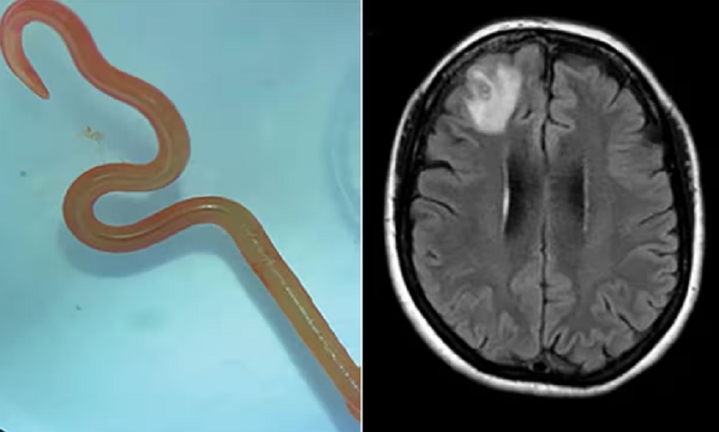

Cận cảnh con giun và vùng não thể hiện tình trạng bất thường ở bệnh nhân.

Đến tháng 1/2022, người phụ nữ bắt đầu mắc chứng hay quên và dấu hiệu trầm cảm ngày càng trầm trọng. Những triệu chứng này khiến các bác sỹ phải kiểm tra não của bà. Họ nhận thấy bà có một tổn thương trong não và chỉ định phẫu thuật. Trong ca mổ, các bác sỹ rất sốc khi nhìn thấy một con giun ký sinh trong não và họ càng choáng váng hơn khi nó ngọ nguậy.

Sau khi phân tích, họ xác định đây là một con giun đũa có tên khoa học Ophidascaris robertsi. Đội ngũ y bác sĩ của Bệnh viện Canberra cho rằng đây là trường hợp đầu tiên trên thế giới phát hiện giun đũa trong não người.

Con giun lấy ra từ não bệnh nhân.